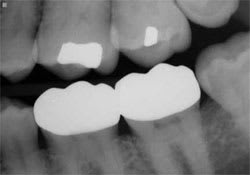

Figure 1 Case 1, preoperative condition. | Figure 2 Case 1, prepared and isolated. | ||||||

Radiographic findings: Teeth Nos. 18 and 19 had deep amalgam restorations and sound interproximal bone levels. Tooth No. 18 had evidence of a sedative base.